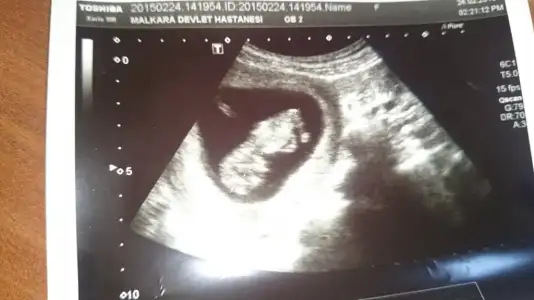

dr soylemeden siz gorun genital nub teorisi ( bebegin cinsiyeti)

• CAM00163.webp

CAM00163.webp

19,8 KB · Görüntüleme: 127